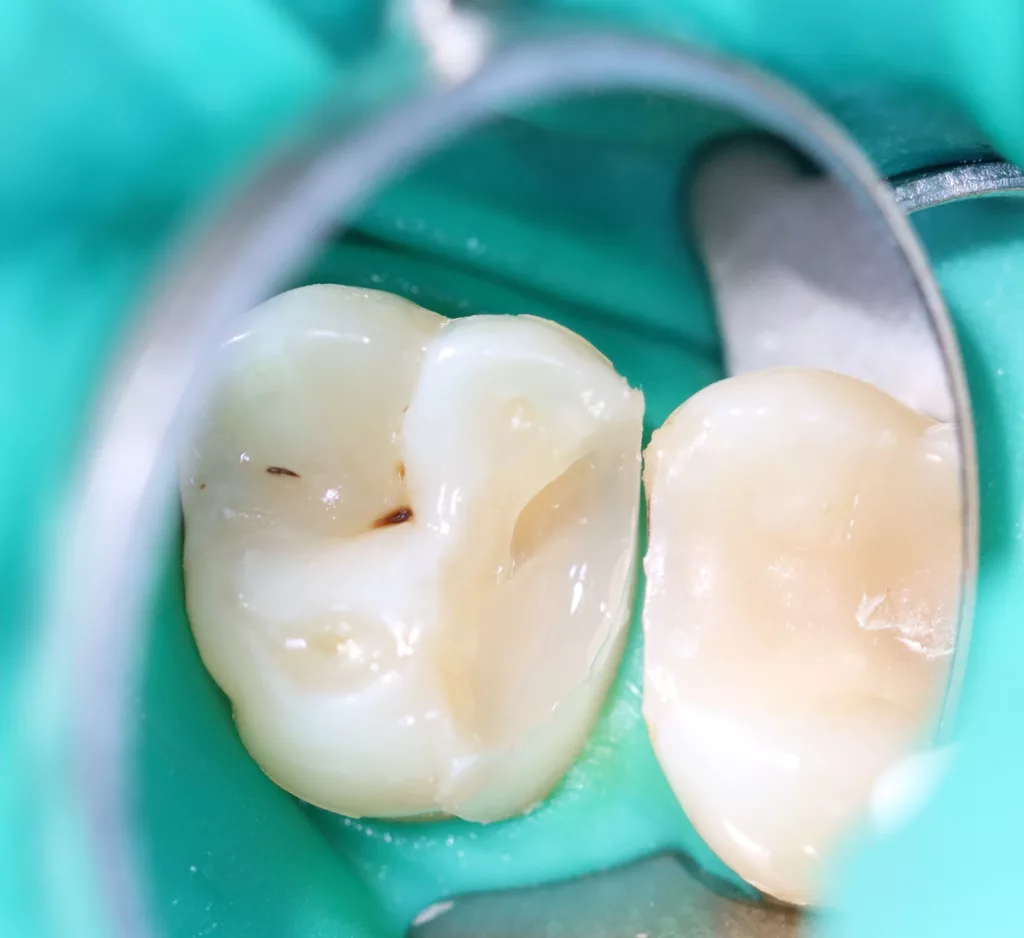

Wird eine profunde kariöse Läsion behandelt, empfiehlt sich folgendes Vorgehen [5]: Zunächst sollte in einem ersten Schritt ein Kofferdam appliziert werden, um eine möglichst keimfreie Arbeitsweise zu gewährleisten. Nach Präparation einer Zugangskavität, wenn dies notwendig ist, erfolgt die Kariesexkavation mittels Rosenbohrern oder Handexkavatoren. Wird in pulpanahen Arealen eine Eröffnung der Pulpa erwartet, sollte das Instrument gewechselt und ein sauberer Rosenbohrer genutzt werden. Tritt nach vollständiger Kariesexkavation keine Eröffnung der Pulpa ein, ist aber von einer dünnen Restdentindicke von etwa 300 µm auszugehen, oftmals erkenntlich durch eine zartrosa hindurchschimmernde Pulpa, sollte nach Kavitätentoilette mittels Natriumhypochlorit (NaOCl) 3% eine indirekte Überkappung mit einem hydraulischen Kalziumsilikatzement erfolgen [5]. NaOCl dient dazu, Bakterien und Toxine zu neutralisieren und das Dentin zu desinfizieren. Die Unterfüllung aus Kalziumsilikatzement soll auch desinfizierend wirken, das Pulpagewebe zur Heilung anregen und vor möglicherweise durch das Dentin penetrierenden Monomeren aus dem Dentinadhäsivsystem schützen [5], da diese die regelrechte Funktion der Odontoblasten beeinträchtigen können [9,40]. Im Anschluss muss eine direkte, dentinadhäsive Restauration zur Versorgung der Kavität platziert werden [5]. Die Abbildungen 1 bis 14 illustrieren das Vorgehen bei der Behandlung einer profunden kariösen Läsion mit indirekter Überkappung der Pulpa.